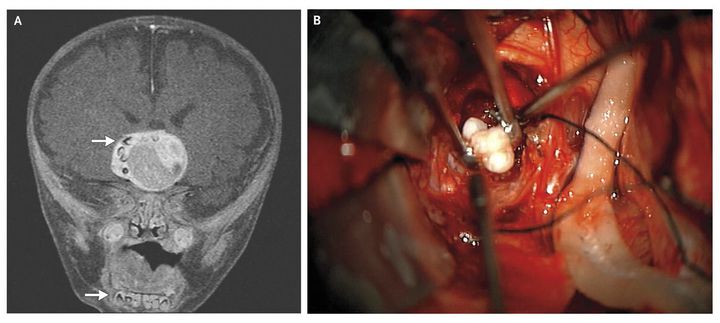

A 4-month-old term male infant presented with increasing head circumference on routine pediatric visits. Magnetic resonance imaging (MRI) of the brain revealed a heterogeneous, enhancing suprasellar mass (4.1 cm by 4.0 cm by 3.5 cm) on T1-weighted images after the administration of contrast material (Panel A). Multiple structures along the right periphery of the mass showed characteristics similar to those of teeth in the mandible (arrows). The patient underwent tumor resection through a right pterional approach; multiple fully formed teeth were seen in the tumor mass (Panel B). On pathological examination, an adamantinomatous craniopharyngioma was identified, which is a slow-growing tumor arising from Rathke's pouch, an embryonic precursor to the anterior pituitary. Such tumors consist of organized stratified squamous epithelium and wet keratin (keratin nodules) and may be cystic; the cysts are filled with viscous, yellow fluid containing cholesterol crystals. Histologically, adamantinomatous craniopharyngiomas closely resemble some odontogenic tumors and cysts. In the year since he underwent surgery, the patient has required shunting for bilateral subdural hygromas and receives thyroid and adrenal hormone-replacement therapy. He is making good developmental progress, and as part of his follow-up, he currently undergoes routine MRI.